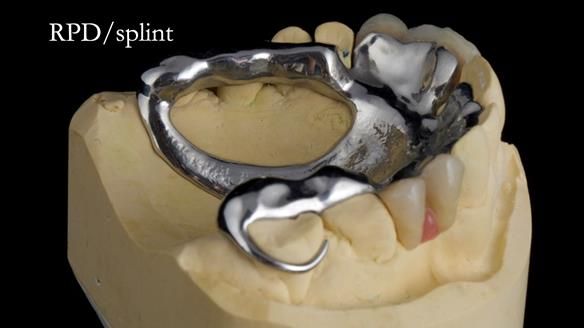

Welcome to Newsletter 67, where I will detail the making and fitting of an upper metal-based partial denture/splint (“Combat denture”) for Brian, a patient with a powerful locked occlusion and deep overbite. The full protocol workflow is presented here.

- Bruxism: The upper and lower teeth are worn and chipped due to heavy clenching and grinding. With a powerful bite and limited space for replacement teeth, dental implants supported fixed teeth are not recommended. A simpler solution is a metal-based partial denture/splint (“Combat denture”) as planned below. This will act as a splint to protect and replace the missing teeth.

Treatment Process: I provided the clinical work, while Rowan Garstang handled the technical work. The treatment required five visits to fit the RPD. The worn lower anterior teeth were then built up. Unfortunately, I did not check the guidance on the denture teeth after this, and tooth 11 fractured off the denture. Brian was very understanding, and I adjusted the denture thoroughly. It has been fracture-resistant and trouble-free for the last three years.